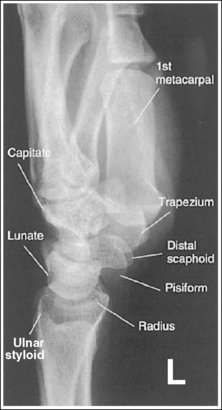

See Figure 4-29 and Box 4-11.

Contrast and density are adequate to demonstrate the scaphoid fat stripe.

• Significance of the scaphoid fat stripe. The scaphoid fat stripe is one of the soft tissue structures that should be visible on all PA wrist projections (Figure 4-30). It is convex and located just lateral to the scaphoid in an uninjured wrist. A change in the convexity of this stripe may indicate to the reviewer the presence of joint effusion or of a radial side fracture of the scaphoid, radial styloid process, or proximal first metacarpal.

The wrist is positioned in a PA projection. The radial and ulnar styloids are at the extreme lateral and medial edges, respectively, of each bone. The radioulnar articulation is open, and superimposition of the metacarpal bases is limited.

• Rotation of the wrist and forearm is controlled by the position of the hand, elbow, and humerus. A PA projection is accomplished by abducting the humerus until it is positioned parallel with the IR and the elbow is in a lateral projection. The hand is then pronated, placing the wrist in a PA projection (Figure 4-31).

The carpal bones are at the center of the exposure field. The carpal bones, one fourth of the distal ulna and radius, and half of the proximal metacarpals are included within the collimated field.

• The wrist joint is located at a level just distal to the palpable ulnar styloid. To obtain an image of the carpal bones with the least amount of distortion, place a perpendicular central ray at this level and centered to the midwrist area. Open the longitudinal collimation to include half of the metacarpals. Transversely collimate to within 0.5 inch (1.25 cm) of the wrist skin line.